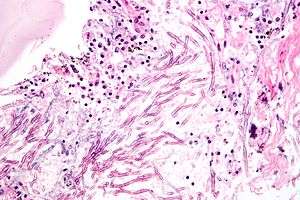

Aspergillus

The most common pathogenic species are Aspergillus fumigatus and Aspergillus flavus. Aspergillus flavus produces aflatoxin which is both a toxin and a carcinogen and which can potentially contaminate foods such as nuts. Aspergillus fumigatus and Aspergillus clavatus can cause allergic disease. Some Aspergillus species cause disease on grain crops, especially maize, and synthesize mycotoxins including aflatoxin. Aspergillosis is the group of diseases caused by Aspergillus. The symptoms include fever, cough, chest pain or breathlessness. Usually, only patients with weakened immune systems or with other lung conditions are susceptible.[1]